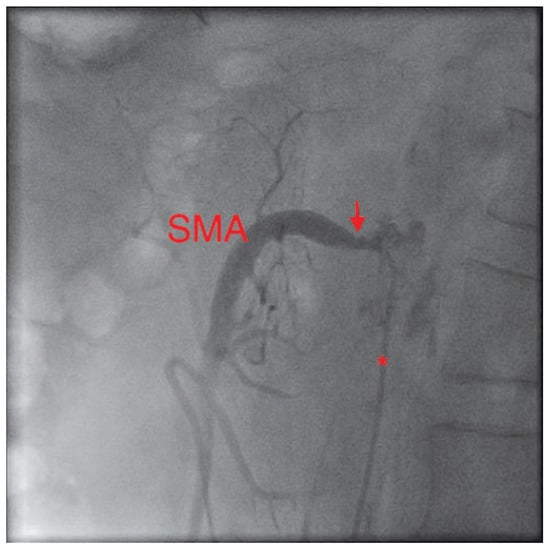

The coronary angiogram showed open coronary bypasses with no relevant progression of coronary atherosclerosis. Due to the clinical picture, suggesting mesenteric ischemia, selective angiography of the major splanchnic arteries was performed. It showed significant stenosis of the proximal superior mesenteric (SMA) and of the proximal celiac arteries (CA). The inferior mesenteric artery (IMA) and both renal arteries were normal.

In a first step, the SMA was treated by balloon angioplasty and a bare metal stent (hippocampus 7.0/20 mm) was implanted. After 2 weeks, the patient was readmitted with improved but not completely resolved abdominal symptoms. The remaining stenosis of the CA was revascularised, using another bare metal stent (hippocampus 6.0/20 mm). During a clinical follow-up of six months, the patient was asymptomatic.

Figure 3. Digital subtraction angiography picture of the proximal celiac artery (CA) and the distal SMA, lateral projection. The catheter (*) lies at the ostium of the severely stenosed CA (arrow) – a guidewire is in place. The patent stent (arrowhead) in the SMA is clearly visible.